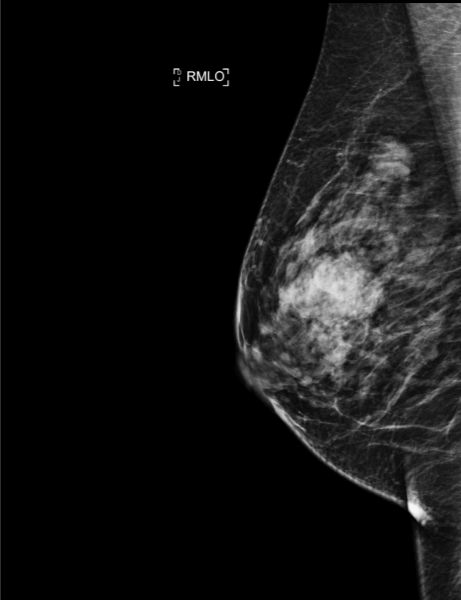

50-year-old woman, screening mammogram.

Mammoscreen® points to an abnormality in the right breast’s outer superior quadrant.

The ultrasound shows a hypoechoic lesion with irregular contours, stiffness is highlighted under elastography.

Microbiopsy confirms a ductal carcinoma SBR II, RH+.